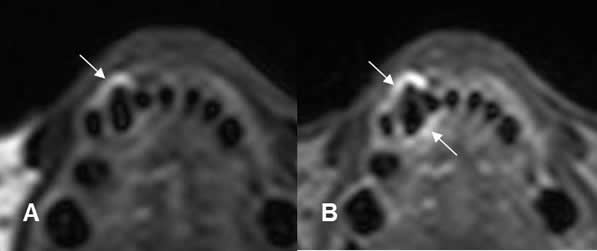

Fig 44. Enfermedad periodontal.

A: RM axial en T2 y B: RM axial en STIR. Cambios inflamatorios y aumento del espacio periapical, por enfermedad periodontal.